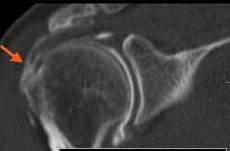

ENTORSA ACROMIOCLAVICULARA

Epansament hipoecogen in sistemul capsulo-ligamentar→

Cu discreta hiperemie la Doppler

Comparatie cu aspectul normal al articulatiei→

Radiografic- aspect normal →